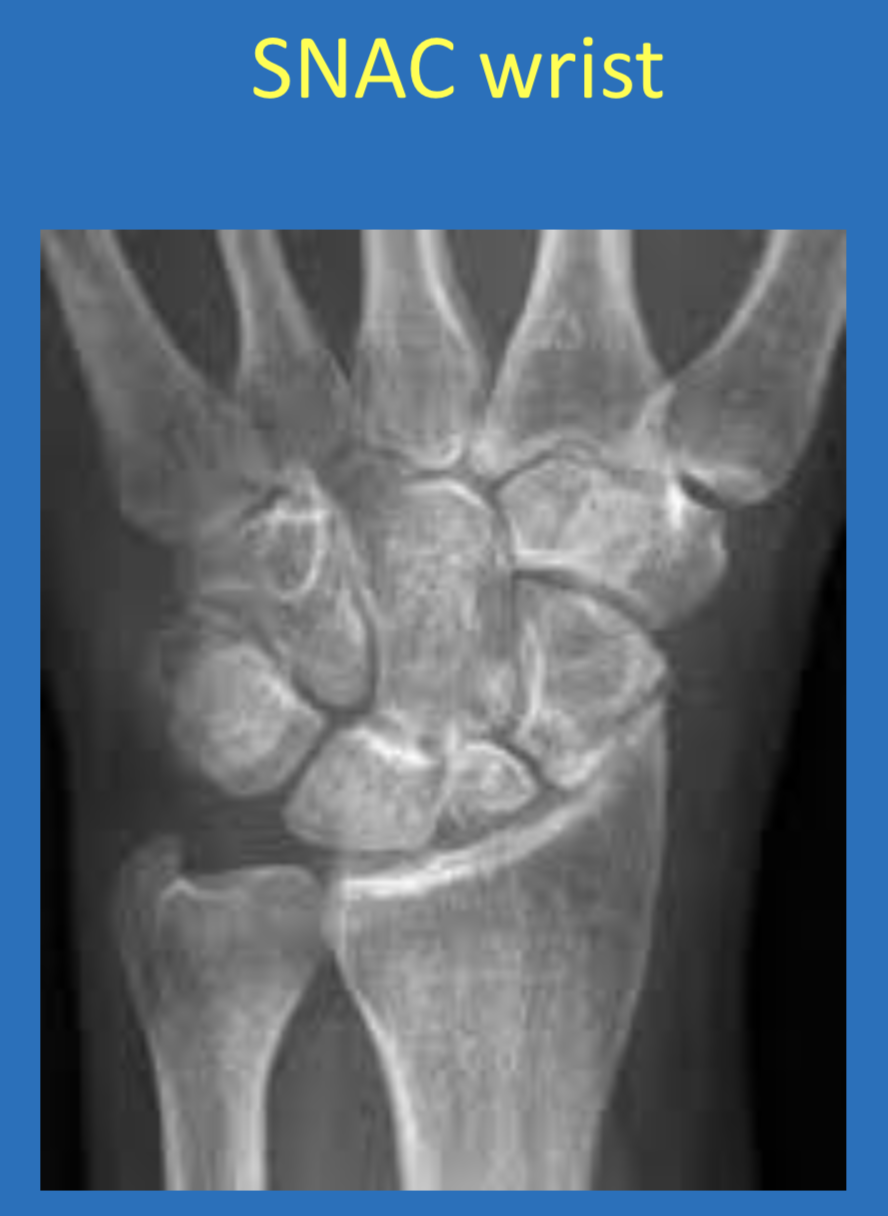

AVN ➞ occurs in the PROXIMAL POLE of the scaphoid

*chance of AVN increases with degree of displacement of fracture